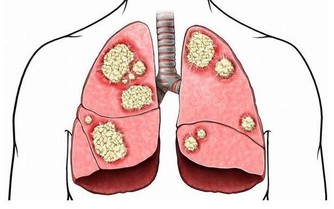

四肢常常抽筋

這也許是缺鈣和維生素D。它們決定骨骼的硬度和肌肉的縮短。要多吃些奶製品、肝臟、海鮮。